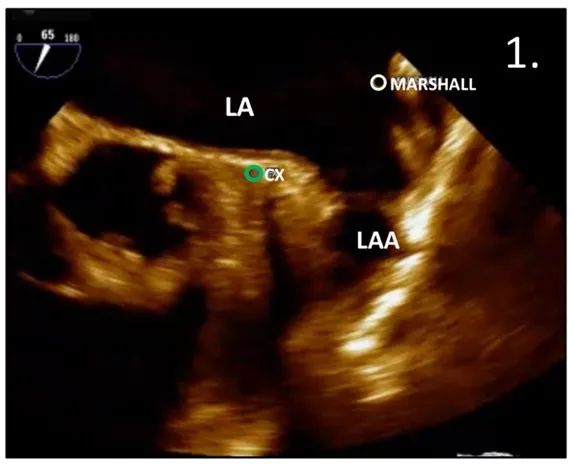

确定左心耳开口标志:Marshell韧带和左回旋动脉

图3:RAO投照中的TSP:白色(Marshell韧带)和绿色(CX)标记表示LAA开口